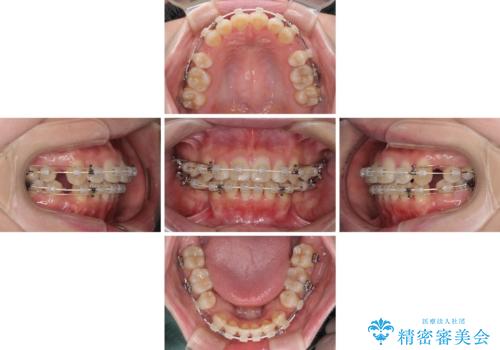

- 審美装置

- 口元の突出感と口の閉じにくさを気にして来院された患者様です。

上下左右第一小臼歯4本を抜歯し、ワイヤー装置にて口元を引っ込めるよう矯正治療を行うこととしました。